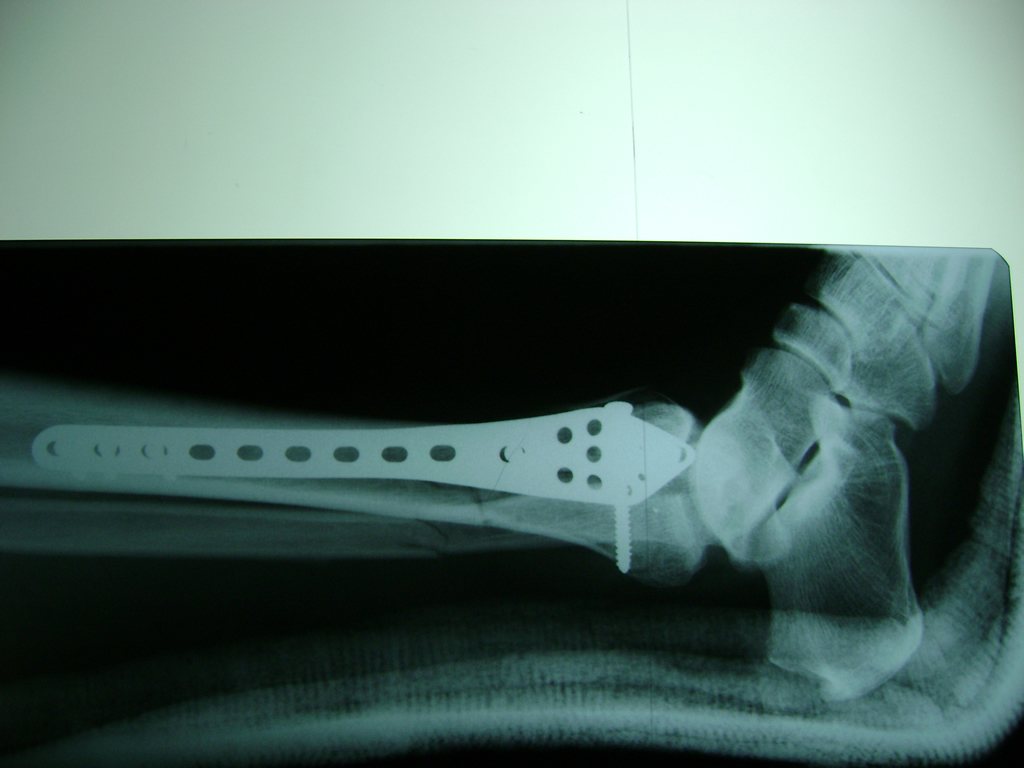

Cuando se necesita cirugía, es probable que esta implique el uso de clavijas de metal, tornillos o placas para sostener los huesos en su lugar mientras la fractura se consolida. Los elementos de soporte pueden ser temporales o permanentes.

Cirugía de Tobi...

Detail Download